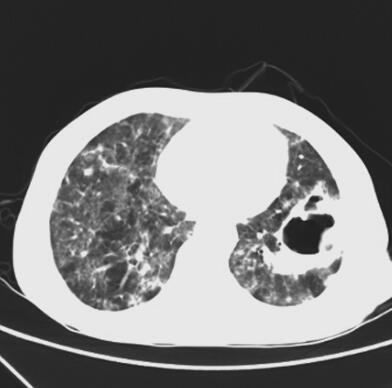

抗生素改用美罗培南、复方磺胺甲噁唑片抗感染,并给予丙种球蛋白静脉滴注,3天后患者体温逐渐下降至正常。血培养未再发现病原菌,继续使用抗生素21天后,患者病情稳定,症状明显好转,复查肺部CT病灶(图2)较前有吸收,给予出院,继续口服复方磺胺甲噁唑片、阿莫西林/克拉维酸钾,并门诊随访,2014年12月1日复查肺部CT(图3),病灶较前明显吸收。

图3 2014年12月1日胸部HRCT

双肺弥漫性斑片影较前明显,左下肺空洞影缩小